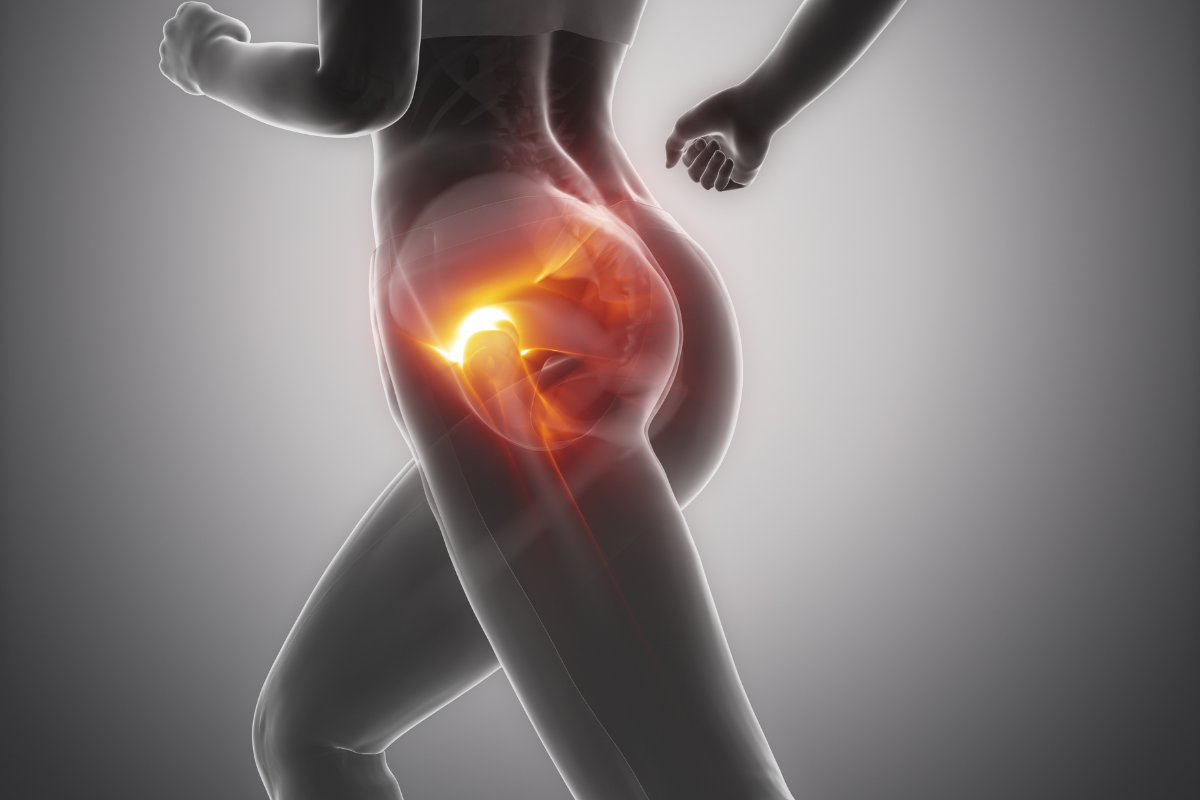

Riabilitazione del pavimento pelvico: sempre più persone, sia donne che uomini, si rivolgono a centri specializzati, perché? Disturbi come incontinenza urinaria, dolore pelvico cronico, prolassi,